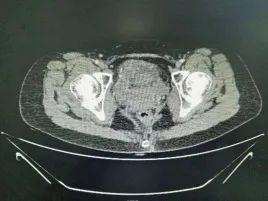

今天做了几台手术,其中一台为宫颈癌根治放疗后中心型复发,并出现膀胱阴道直肠瘘的年轻患者。该患者10天内做了两次,一周前术中谈话患者父亲认为效果差,要求放弃。一周后患者家属再次决定手术。

全盆腔脏器切除,回肠代膀胱,改良bacon术,手术感觉挺彻底。

3.放疗后患者膀胱耻骨间隙比较疏松,可以先断尿道和阴道直肠,采取倒行逆施向上分离。